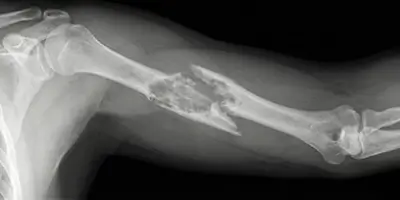

Parçalı kırık (komminüte kırık), kemiğin birden fazla parçaya ayrıldığı ciddi kırık türüdür. Nedenleri, belirtileri, teşhisi ve tedavisi hakkında bilgi.